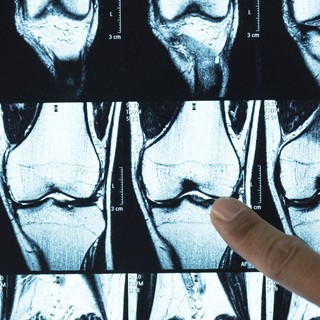

A diagnózis felállításához ortopéd vagy reumatológus szakorvos szükséges, aki a tünetek, a személyes és családi kórelőzmények felmérése, valamint fizikai vizsgálat alapján állítja fel a diagnózist. Képalkotó vizsgálatok, például röntgen vagy MRI is szükségesek lehetnek az ízületi kopás mértékének ellenőrzésére és a legmegfelelőbb kezelés kijelölésére.

• MRI képalkotás: általában nincs rá szükség, kivéve szokatlan körülmények között vagy olyan esetekben, amikor porc- vagy környező szalagszakadás gyanúja merül fel.

Az ortopéd vagy reumatológus szakorvos először fizikális vizsgálatot végez, majd röntgen vagy MR-vizsgálatot kérhet.